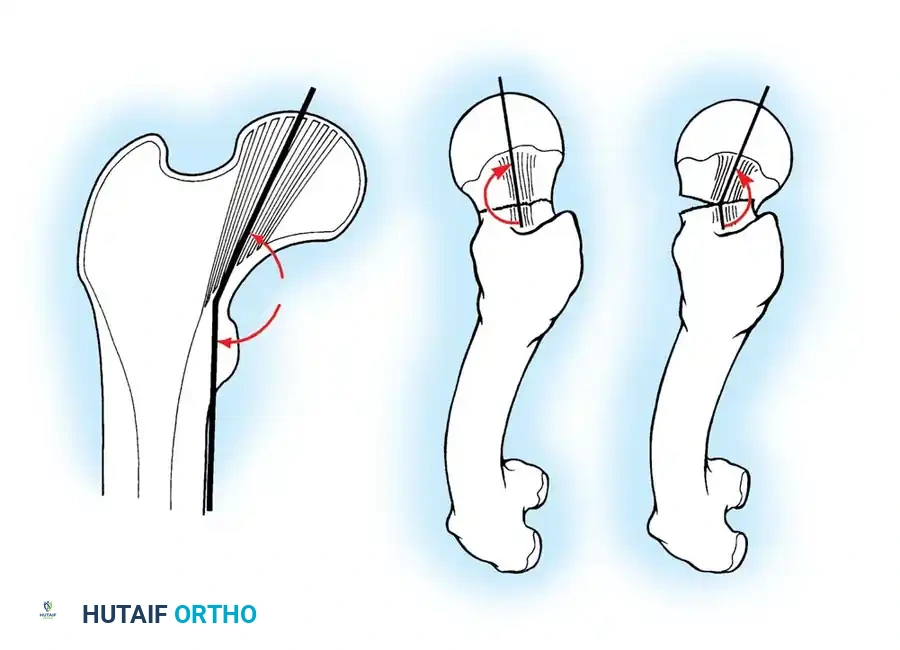

Closed Reduction Maneuver:

1. Apply longitudinal traction to restore leg length.

2. Internally rotate the leg (typically 10 to 15 degrees) to correct the external rotation deformity and bring the femoral neck parallel to the floor.

3. Verify reduction on both AP and lateral fluoroscopic views. An acceptable reduction must have cortical apposition medially and anteriorly.